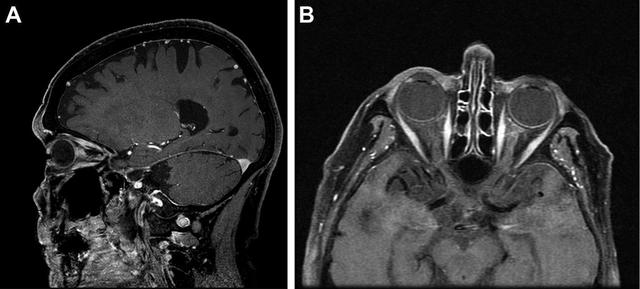

头颅及眼眶增强 MRI 及抑脂相提示左侧视神经的眶段强化(图 2)。左眼视力恶化为无光感。

图 2 A 为增强后矢状面,B 为横断面 MRI,可见左侧视神经眶内段强化、增粗

脑脊液分析示:葡萄糖 113 mg/dL(正常: 40~75 mg/dL,血糖 278 mg/dL),蛋白质 31 mg/dL(正常:15~745 mg/dL),未见细胞。复查眼眶 MRI 提示左侧视神经增粗、强化,较前无变化。胸部 CT 未及结节病或占位迹象。复查发现左眼玻璃体存在浮游细胞。